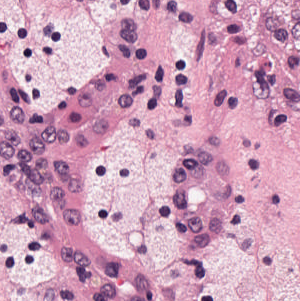

As an essential part of digital pathology, histopathology image analysis is playing increasingly important role in cancer diagnosis, which can provide direct and reliable evidence to diagnose the grade and type of cancer. This paper deals with nuclei segmentation, an important step in histopathological image analysis. The purpose of nuclei semgentation is not only counting the number of nuclei but also obtaining the detailed information of each nucleus. So unlike nuclei detection, here the outputs are the contour of each nucleus instead of only the position of their central points. Hence we can exactly extract each nucleus from the image and make it available for further analysis. For example, the features of the individual nucleus and the distribution of nuclei clusters can be used to grade and classify status of breast cancers [3, 4]. Because of appearance variation such as color, shape, and texture, nuclei segmentation from histopathological images could be very challenging, as illustrated in Fig.1, in which it is very challenging even for human to recognize and segment all nuclei within the images. Fig.1(a) and Fig.1(b) illustrate two histopathological images from different organs. Fig.1(c) and Fig.1(d) are two histopathological images from same organ but have different cancer grade.

H&E stain is the most widely used stain protocol in medical diagnosis. Typically, the nuclei of cells are stained to blue by Haematoxylin while cytoplasm is colored to pink by Eosin. But in practice, the color of H&E stained images could vary a lot due to variation in the H&E reagents, staining process, scanner and the specialist who performs the staining, as shown in Fig.1. A few H&E stain normalization methods[23, 24, 25] have been proposed to eliminate the negative interference caused by color variation. We tried two of them[23, 25] to normalize the raw H&E stained images. For our segmentation algorithm, we did not find any considerable difference between these two normalization methods. Particularly, the result shown in experiment section III is generated based on the images normalized by the method in [23]. Given a target image, this method is able to convert one image’s color into the target image’s color space based on sparse non-negative matrix factorization(NMF). We choose one best stained H&E image as the target and convert other images into its color space. According to the recommendation in [23], the hyper-parameter should be set between 0.01 and 0.1. In our experiment, is set to 0.1.

Figure 6 shows how our method segments the nuclei step by step. The color variety is well controlled by the color normalization procedure. The prediction result shows clear nuclear areas and nucleus boundaries. In the final segmentation result and ground truth image, each nucleus is represented by a different color.